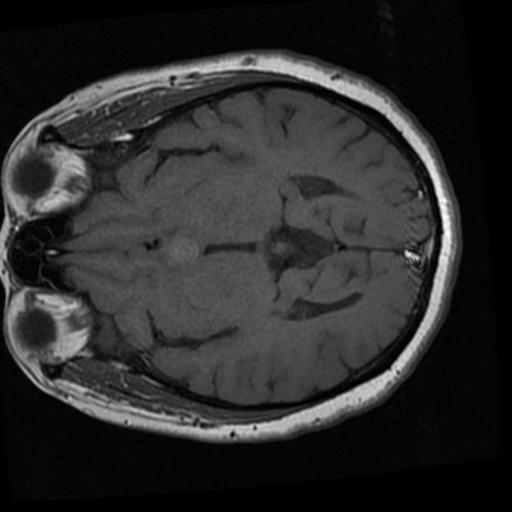

在本教程中,我们将在一个脑部MRI数据集上对MedGemma 4B模型进行微调,以完成图像分类任务。我们的目标是让这个更小的MedGemma 4B模型能够高效、准确地对脑部MRI扫描进行分类,并预测脑癌的存在。

data["train"][18]["image"]